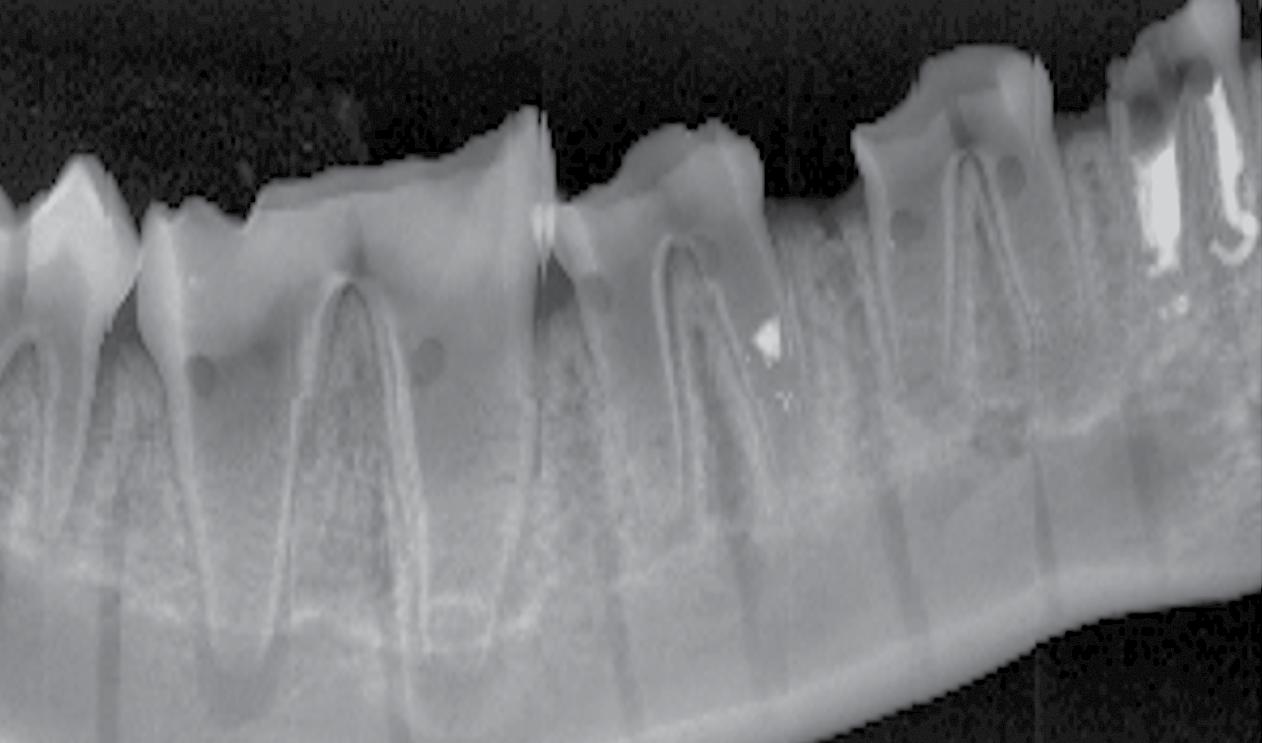

Clinical Need – Based on market research conducted by RevBio, almost half the patients that seek a dental implant supported crown suffer from chronic edentulism and require extensive bone grafting to rebuild their alveolar ridge. Over 30% of the time, these grafting procedures achieve suboptimal results and require some form of re-grafting adding to the overall cost, treatment time, and morbidity for these patients.

Solution – RevBio developed Tetranite® (TN) Adhesive Dental Bone Scaffold (TN-ADBS), a synthetic, porous, cohesive organic-mineral bone scaffold with adhesive properties that resorbs and is replaced by bone on a timescale commensurate with existing graft materials but does not require ancillary fixation or containment devices. The TN-ADBS comprises a kit consisting of the formulation powders sealed in a mixing bowl, a vial filled with highly porous granules, an aqueous medium pre-filled syringe, and spatula for mixing and application to the site.

Competitive Advantage – Currently available particulate bone grafting products require significant surgical skill to apply. In contrast, TN-ADBS is both cohesive and adhesive which enables the placement of the product without the need for ancillary containment or fixation aids. The product will reduce the overall time necessary to perform ridge augmentation procedures, better maintain graft volume over time, and minimize the need for re-grafting, which adds time, cost, and risk to successful patient care.

ITP Support – ITP support has enabled RevBio to accomplish key product development and marketing milestones, including market surveys to validate the clinical need and the lack of any known competitive products with a comparable clinical value proposition, refinement of the preclinical animal model and product formulation, GLP preclinical studies and supplier audits, provision of advice from user handling trials, and regulatory guidance in developing and refining a cohesive strategy for the commercial approval of the product.